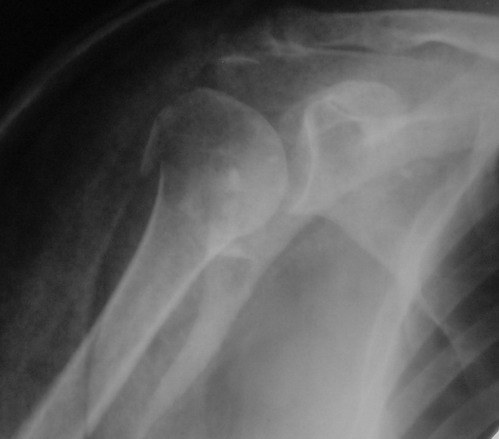

Снимки на 1-е сутки после репозиции и на 8- сутки после репозиции.

Никто не отменял функционального консервативного метода лечения. Дело не только в том, что перелом сросся, вопрос в каком положении.

При переломах хирургической шейки плеча ротаторная манжетка ротирует фрагмент головки внутрь, поэтому при неустраненном упомянутом смещении

перелом рано или поздно срастется, но отведение плеча будет страдать. Очень практичен и функционален метод А.Ф. Лазарева, о котором упомянул Джолдас, ранее обсуждался на форуме , попробуйте, больные будут довольны

результатом.